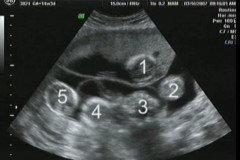

7 Դեկտեմբեր, 2016 11:05

65-ամյա կնոջ լնդի միջից դուրս բերածը շոկի մեջ գցեց բժիշկներին (լուսանկարներ 16+)